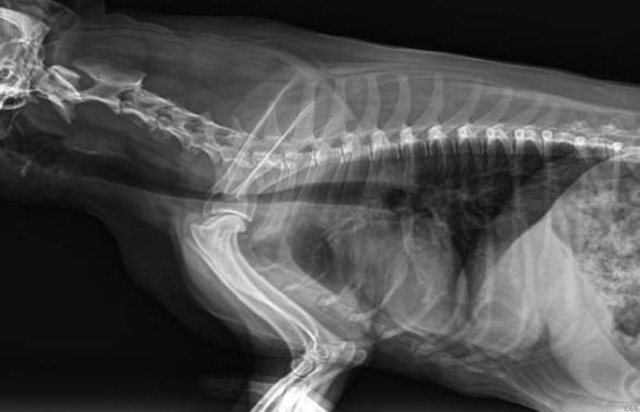

從臨床角度出發(fā),大力發(fā)展動態(tài)DR,以精準(zhǔn)的診斷為小動物保駕護航。寵物DR升級使用雙焦點球管,大尺寸平板探測器,超高頻逆變高壓發(fā)生器。醫(yī)用纖維板臺面,防止寵物劃傷。寵物DR整機小巧實用,骨略結(jié)構(gòu)和器官位置,分類詳細,運算更快,讓拍攝條件更科學(xué),有助于提高診斷的準(zhǔn)確性和效率。安裝移動非常方便。低輸入電流設(shè)計,220伏常規(guī)電壓。多品種動物程序設(shè)定,滿足各個臨床需求。成像效果顯著,寵物不能言語表達,導(dǎo)致誤診率居高不下。寵物診療均以經(jīng)驗診斷為主的方式,確保最小化輻射降低對醫(yī)生及動物的影響。以滿足精細化的寵物醫(yī)療需求,成為診斷寵物內(nèi)外科疾病的必備工具。使醫(yī)院更有競爭力,為醫(yī)院創(chuàng)收增光添彩。

寵物DR的操作流程是什么呢?第一步首先插上整機電源,然后按下主機電源。打開高壓發(fā)生器的電源,工作站主機電源。等待主機軟件的自動啟動。通過軟件登記檢查的寵物信息,選擇寵物檢查拍攝部位。調(diào)節(jié)限速器拍攝區(qū)域。關(guān)閉鉛房門,點擊開始拍攝按鈕。拍攝完成調(diào)整圖像并且輸出。